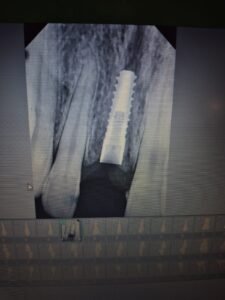

Step 1 — Implant Placement The titanium implant fixture was surgically placed into the healed bone site with precision. The post-placement X-ray confirms ideal positioning — the implant is perfectly seated within the bone, in correct angulation and depth, with healthy bone visible on all sides.